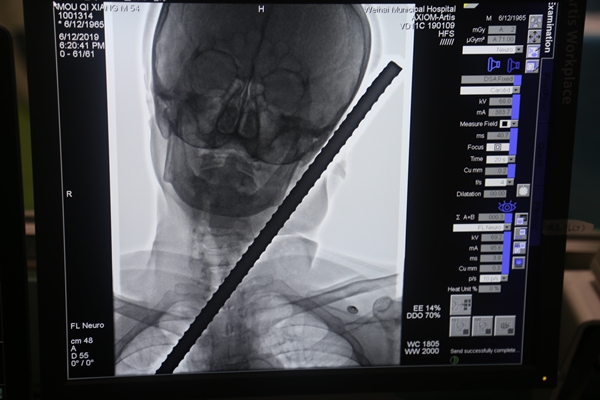

当日18时许,在市立医院介入手术室,一名男子躺在大型设备上,正在进行造影检查。一根螺纹钢筋从他的下颌左侧穿入后从左耳旁刺出,在扎入和刺出部位都裸露着表面带有铁锈的钢筋头,还有渗血并伴血凝块形成。

此时,在介入手术室外间,来自口腔、介入放射、耳鼻咽喉头颈外科等科室的专家正围在电脑前,面色凝重地盯着电脑显示屏显示的各个角度的3D图像,仔细查看着插入男子面部的钢筋走向、所伤及的部位等。

“钢筋自下颌升支后缘,下颌后窝处穿入,颈动脉只有颞浅动脉断裂,外耳道有损伤。”随着检查结果出炉,现场的紧张气氛一下子得到了缓解,专家们也稍微松了口气:“伤者实在太幸运了,虽然有一些损伤,但钢筋在进入体内时巧妙地避开了面神经总干、颈动脉等重要部位,算是躲过了一劫。”根据检查情况,专家进行了分析评估。随后,对于断裂的颞浅动脉,立即进行了栓塞止血处理。